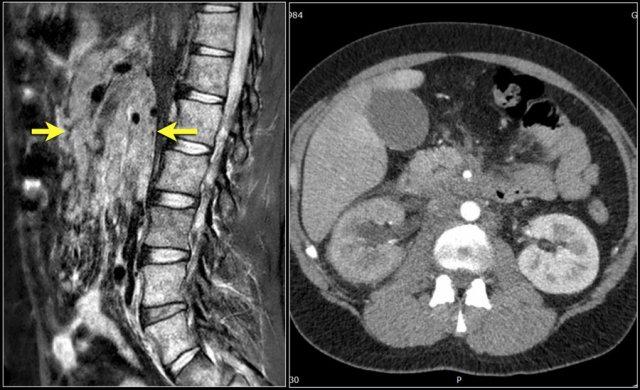

Các mô trước cột sống

Đây là bệnh nhân 25 tuổi nhập viện vì đau thắt lưng.

Lưu ý nhiều khối nhỏ trong ổ bụng bao quanh các mạch máu mạc treo và tín hiệu tủy xương giảm bất thường.

Tín hiệu của đĩa đệm cao hơn một chút so với tủy xương (dấu hiệu đĩa đệm sáng – bright discus sign).

Đây là dấu hiệu đầu tiên cho thấy bất thường ở bệnh nhân này.

Kết quả cho thấy đây là di căn xương và hạch bạch huyết từ ung thư đại tràng.

Đây là một bệnh nhân khác với hình ảnh nổi hạch bạch huyết lan rộng tại mạc treo ruột và sau phúc mạc.